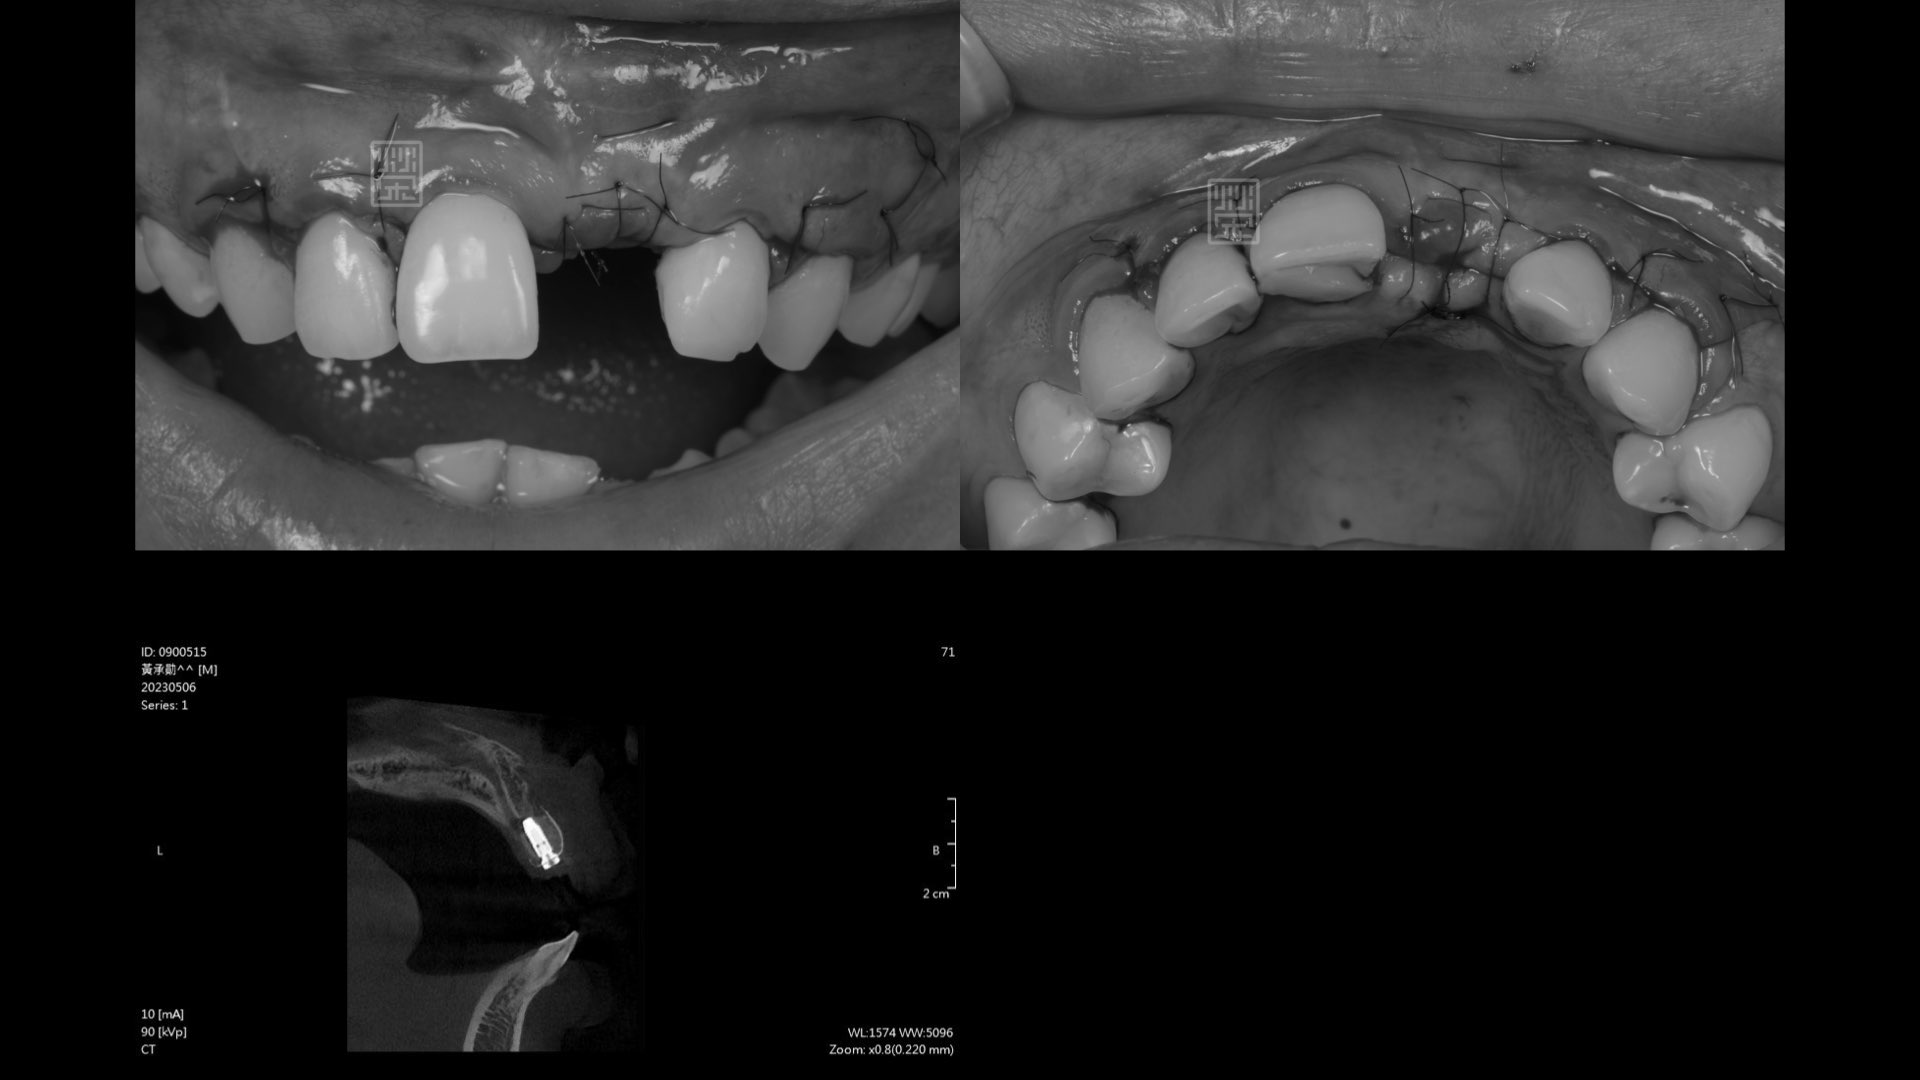

植牙與再次補骨

接出植牙支台

牙齦軟組織重建